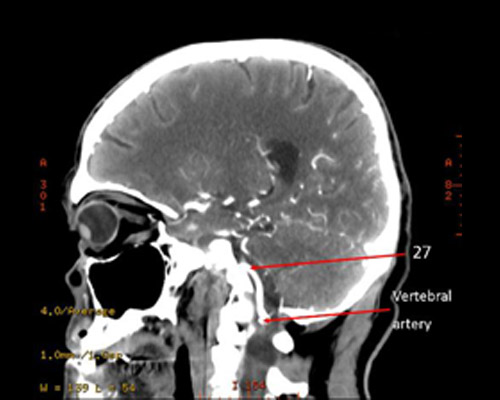

27?

27 = basilar